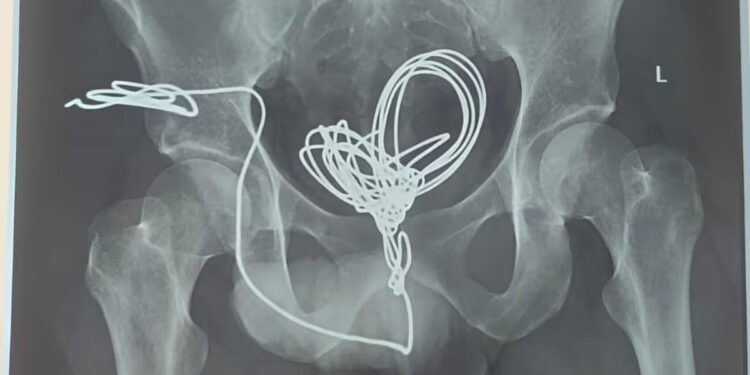

തിരുവനന്തപുരം: മൂത്രനാളിയിലൂടെ സ്വയം കുത്തിക്കയറ്റിയ ഇലക്ട്രിക് വയർ യുവാവിന്റെ വയറ്റിൽ നിന്ന് ശസ്ത്രക്രിയയിലൂടെ പുറത്തെടുത്തു. തിരുവനന്തപുരം സ്വദേശിയായ 25കാരനാണ് മൂന്ന് മീറ്ററോളം നീളമുള്ള ഇലക്ട്രിക് ഇൻസുലേഷൻ വയർ മൂത്രനാളിയിലൂടെ കുത്തിക്കയറ്റിയത്. ആശുപത്രിയിലെത്തുമ്പോൾ വയർ മൂത്രസഞ്ചിയിൽ കുരുങ്ങിക്കിടക്കുന്ന നിലയിലായിരുന്നു. എന്നാൽ യുവാവ് ഇതു ചെയ്തതിന്റെ കാരണം വ്യക്തമല്ലെന്ന് അധികൃതർ പറഞ്ഞു. തിരുവനന്തപുരം മെഡിക്കൽ കോളജ് ആശുപത്രി യൂറോളജി വിഭാഗത്തിൽ വയർ തുറന്നു നടത്തിയ ശസ്ത്രക്രിയയിലൂടെയാണ് പല കഷ്ണങ്ങളായി മുറിച്ച് ഇലക്ട്രിക് വയർ പുറത്തെടുത്തത്. ശസ്ത്രക്രിയ രണ്ടര മണിക്കൂറോളം നീണ്ടു. […]